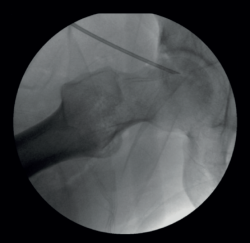

After treatment of the concomitant disorders, the femoral head lesion was visually identified and the absence of femoral head collapse at the site of necrosis was checked arthroscopically (Figure 6).

Six perforations were made with the guide of the 1.3 mm anchors (Y-Knot® Flex) and three perforations were made with the guide of the 2.8 mm knotless PEEK anchors (PopLok® Knotless Suture Anchor) for CD of the femoral head through the anterolateral region of the femoral neck under visual guidance, establishing a separation of 3 mm between them, with a diameter of 1.3 mm and 2.8 mm, respectively, and checking bleeding of each perforation (Figure 7 and Video 1).

Figure 3. Arthroscopic acetabuloplasty using the over-the-top technique. Control of the procedure with image intensifier.

Figure 7. Core decompression of the femur through microperforations; arthroscopic view and fluoroscopic control.